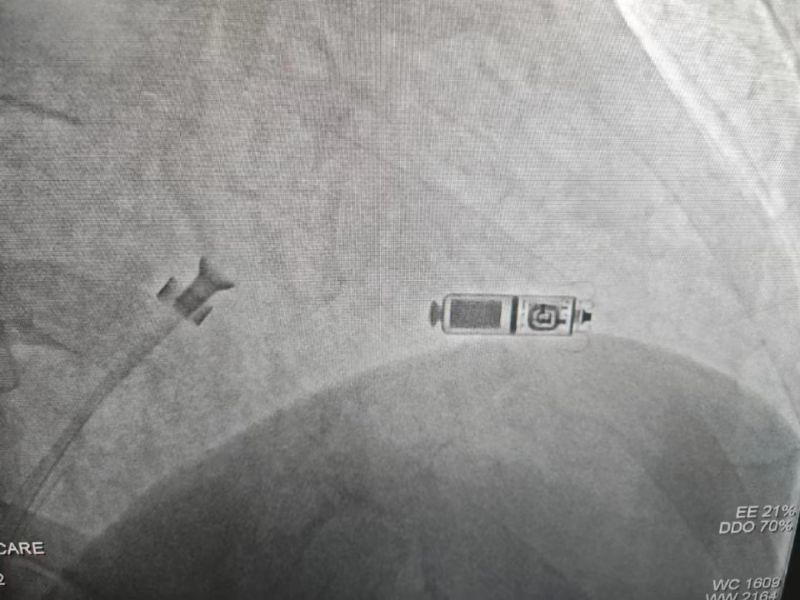

手術(shù)過程:經(jīng)過充分的術(shù)前討論,在延安大學(xué)咸陽醫(yī)院心血管病院吳棟梁院長(zhǎng)、劉雄濤副院長(zhǎng)的指導(dǎo)與支持下,李陽教授、何克強(qiáng)主治醫(yī)師、辛浩主治醫(yī)師與導(dǎo)管室介入團(tuán)隊(duì)的共同努力下,經(jīng)過超聲科、心電中心等多學(xué)科協(xié)作,成功為患者植入雙腔無導(dǎo)線永久起搏器,術(shù)后第二天患者在起搏器保障下經(jīng)藥物治療恢復(fù)正常的竇性心律。目前患者心臟情況及腦梗均恢復(fù)良好,已順利出院。

科普:Micra無導(dǎo)線起搏器號(hào)稱“世界最小起搏器”,無需植入心內(nèi)膜導(dǎo)線,也無需在胸前皮下制作囊袋放置脈沖發(fā)生器(起搏器),手術(shù)僅需局部麻醉,通過股靜脈穿刺,將起搏器經(jīng)導(dǎo)管植入心腔內(nèi),手術(shù)時(shí)間短,減少出血、血腫及感染風(fēng)險(xiǎn),術(shù)后恢復(fù)快,肢體活動(dòng)不受限,無異物感。

優(yōu)勢(shì):比傳統(tǒng)起搏器體積減少93%,體積更小,重量?jī)H2g,類似一顆維生素膠囊;雖體積只有傳統(tǒng)起搏器十分之一,但其小小身體儲(chǔ)存大能量,續(xù)航時(shí)間超過12年,整個(gè)手術(shù)過程平均約30分鐘,植入成功率高,術(shù)后8-12小時(shí)即可下床活動(dòng),術(shù)后1-2天即可出院;兼容1.5T(特斯拉)/3.0T全身核磁共振掃描。滿足患者植入Micra之后疾病的診斷和治療需求。